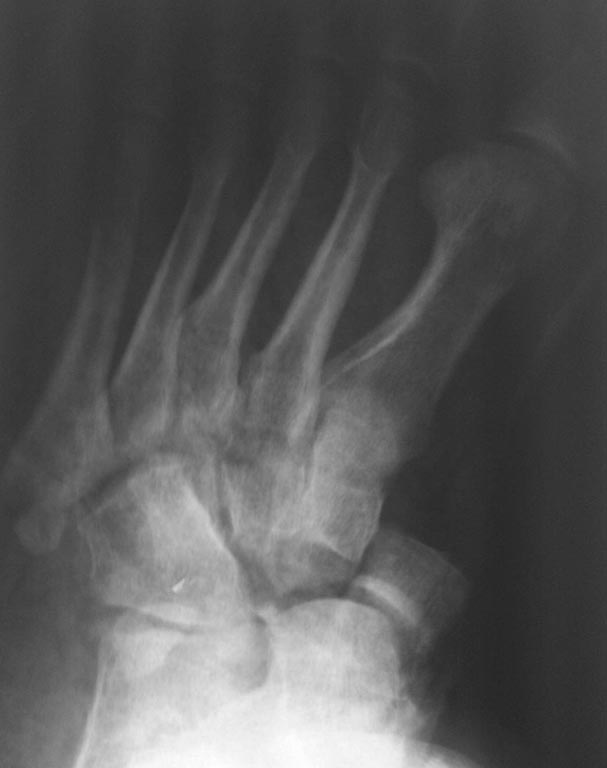

[Ortho] застарелый переломовывих в суставе Шопара

Обратился пациент 40 лет через 2,5 мес после травмы,

не курит, социален. Первым этапом наложили дистрактор, дозированная

дистракция, вторым этапом планировали репозицию ладьи с bridge plate

(шейка - клин). После выходных обнаружили такую картинку некрозов,

доступ планировался именно так. Считаю, что основная проблема в

ладье. Фрагмент ладьи абс неподвижен. Вопросы: стоит рисковать или нет?

будет ли менее рискованная операция позже по рубцу? Что еще следует

учесть (возможно недопонимаю анатомию повреждения)? Другие варианты?